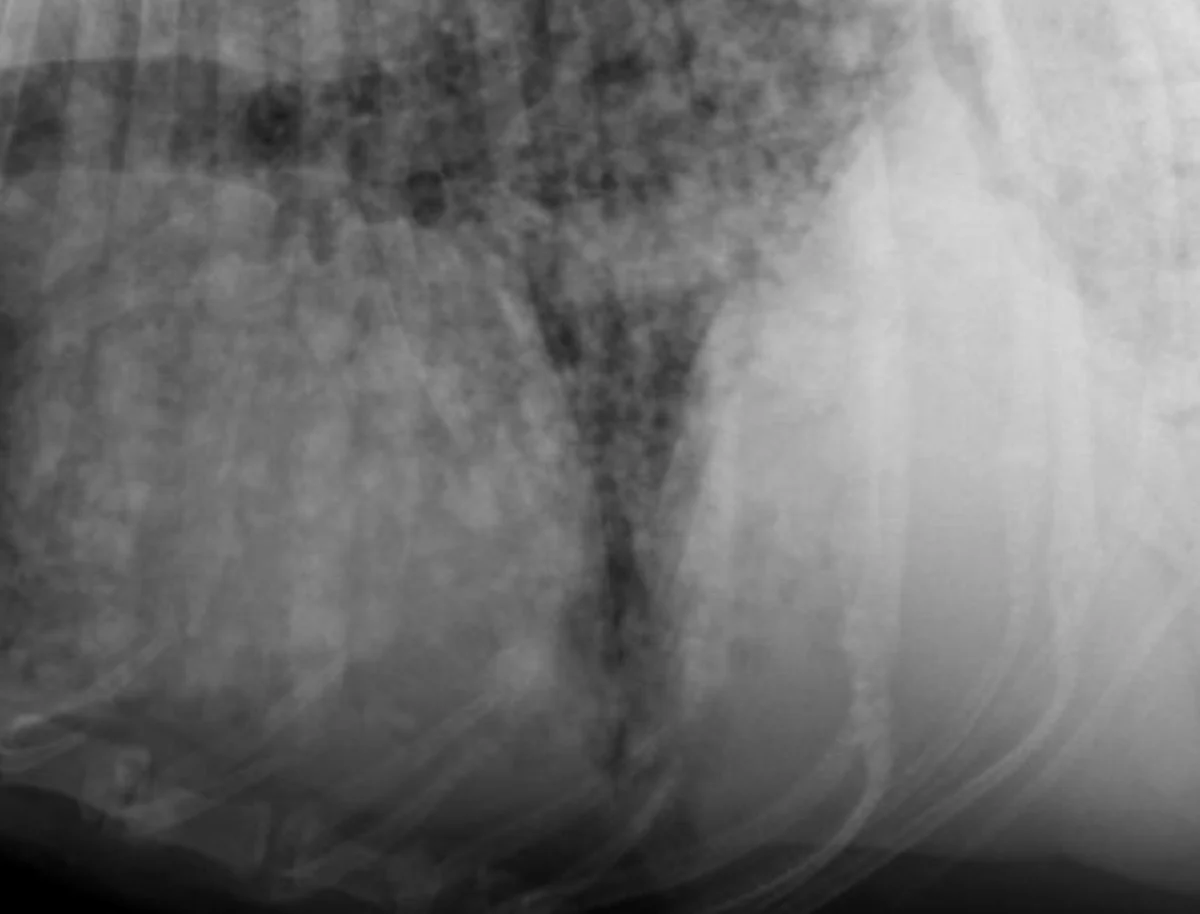

With increased opacity, many diseases will present with a mixed pulmonary pattern, so the dominant pattern should be identified to formulate an appropriate differential list (Figure 5). More important, the anatomic distribution will drive the prioritization process for differentials. For example, cranioventral typically equates with infectious disease (bacterial pneumonia), whereas caudodorsal typically equates with edema (cardiogenic or noncardiogenic).

Lateral radiographs from various dogs with increased lung opacity; ventral alveolar pulmonary pattern (A), generalized bronchial pulmonary pattern (B), vascular pulmonary pattern in a dog with a left-to-right shunting patent ductus arteriosus (C), structured interstitial pulmonary pattern in a dog with pulmonary nodules secondary to renal carcinoma metastatic disease (D), and an unstructured interstitial pulmonary pattern (E)